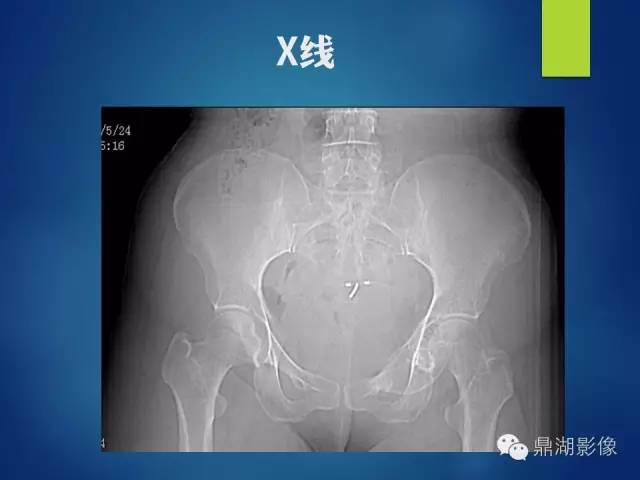

【病例】耻骨黏液型软骨肉瘤1例X线CT影像表现

-主 诉:发现左腹股沟肿物伴左髋关节活动受限10余年

-专科检查: 脊柱呈正常生理弯曲,各棘突未及压痛及叩击痛。左腹股沟区肤色正常,可触及一约7cm*5cm肿物,质软稍韧,活动度差。左腹股沟区肿物压痛(-),叩击痛( -)。左下肢感觉正常,左髋关节主被动屈曲活动稍受限,伴弹响。双上肢感觉及活动可。末梢血运感觉可。双下肢肌力正常。生理反射存在,病理反射未引出。

影像表现:

左侧耻骨可见一不规则略低于软组织密度影,周围骨皮质变薄,其内可见丝瓜囊样密度增高影,未见明显骨膜反应及骨折线。